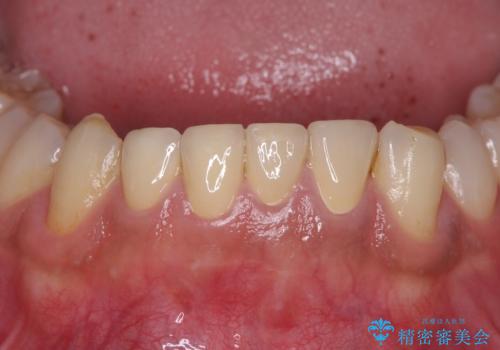

[前歯の変色] 前歯の見た目を改善したい

前歯が黒い セラミックで綺麗に 20代女性

前歯の見た目を改善したい